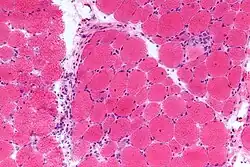

The pathogenesis of dermatomyositis involves an autoimmune-mediated process characterized by immune complex deposition and complement activation, leading to microangiopathy in both muscle and skin tissues. The specific mechanism of tissue injury is variable, depending on the specific autoantibodies and immune cell types involved.[16] The microangiopathy has a non-uniform pattern: within a single muscle fiber, some capillaries may be heavily affected while others seem to be unharmed.[17]

In contrast to polymyositis, which pathologically centers on damage to the endomysium of muscle fibers, dermatomyositis damages both the endomysium and the perimysium. This indicates that tissue damage from dermatomyositis is not limited to the capillaries and the tissues immediately surrounding them; it also damages the larger vessels of the muscle fibers and skin tissue, potentially causing wider structural damage.[17]

The complement system plays a crucial role in the tissue injury of dermatomyositis, through the formation and deposition of immune complexes. Autoantibodies target muscle and skin antigens, leading to the activation of the classical complement pathway, ultimately forming the membrane attack complex (MAC) on the endothelial cells of microvasculature.[3] MAC causes direct endothelial cell damage by perforating the cell membrane and ultimately lysing (destroying) the cell due to osmotic effects.[18] The destruction of vascular endothelium results in increased vascular permeability, furthering the pro-inflammatory immune cell infiltration of the tissue, and also results in tissue ischemia due to the lack of blood flow. Additionally, complement fragments facilitate the recruitment and activation of inflammatory cells like macrophages and T lymphocytes, further driving the inflammatory response and resulting damage to local tissue. However, the specific sequence of complement activation is not completely understood and may depend on the pathological subtype of the disease.[3][19]

- Examining a muscle biopsy under a microscope and finding mononuclear white blood cells between the muscle cells, and finding abnormal muscle cell degeneration and regeneration, dying muscle cells, and muscle cells being consumed by other cells (phagocytosis)